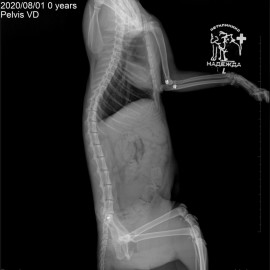

Котик Персик после покуса собаки. Обратились с жалобами на отсутствие опороспособности на левую переднюю и задние лапы. После рентгенографического исследования поставлен диагноз: вывих левого локтевого сустава, перелом костей правого крестцово-подвздошного сочленения, перелом лонной и седалищной костей таза. Проведена операция: остеосинтез левого локтевого сустава, остеосинтез правого крестцово-подвздошного сочленения таза.

Снимки 1-2 до операции